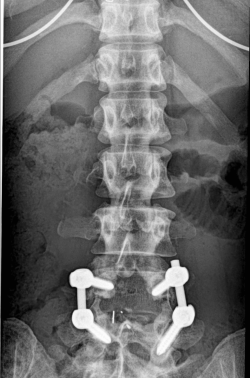

Во время первой консультации в больнице в Сеуле, когда хирург посмотрел снимки металлической конструкции, что мне поставили в нашей стране, он был в шоке. Такую конструкцию в позвоночник нельзя устанавливать вообще, сказал он, так как человек постоянно двигается, садиться, наклоняется, поэтому конструкция должна быть динамическая, из современного титанового сплава. А в моей спине были просто прикрученные болты и гайки.

Без оснований на то, еще и в трех позвонках. В общем, полная некомпетенция наших врачей - шарашкина контора, а ведь речь идет о жизни человека. Нет слов, делают все на авось, лишь бы денег срубить. Когда меня прооперировали в Сеульской больнице, после операции мне вручили наш отечественный "имплант", что вынули из меня. Это были просто железные болты, похожие на те, что вкручивают в мебель. Но я же не мебель, я человек, который разгибается и сгибается, и двигается в конце концов. Теперь вы понимаете, почему операция, которую сделали у нас, не могла дать качественного результата? А потому, что технологии медицинские, оснащение и оборудование очень древние и устаревшие. Я закопала те болты под деревом, чтобы навсегда забыть этот страшный сон.